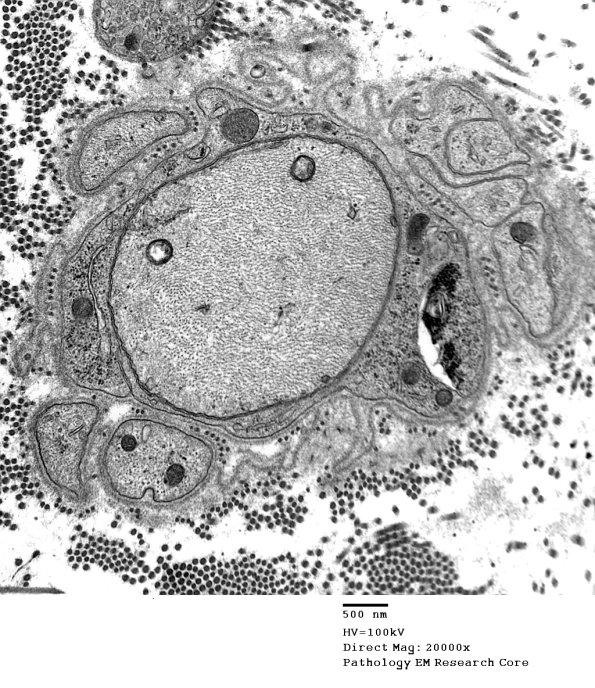

Additional demyelinated axons, some of which show redundant myelin loops. (electron micrographs)